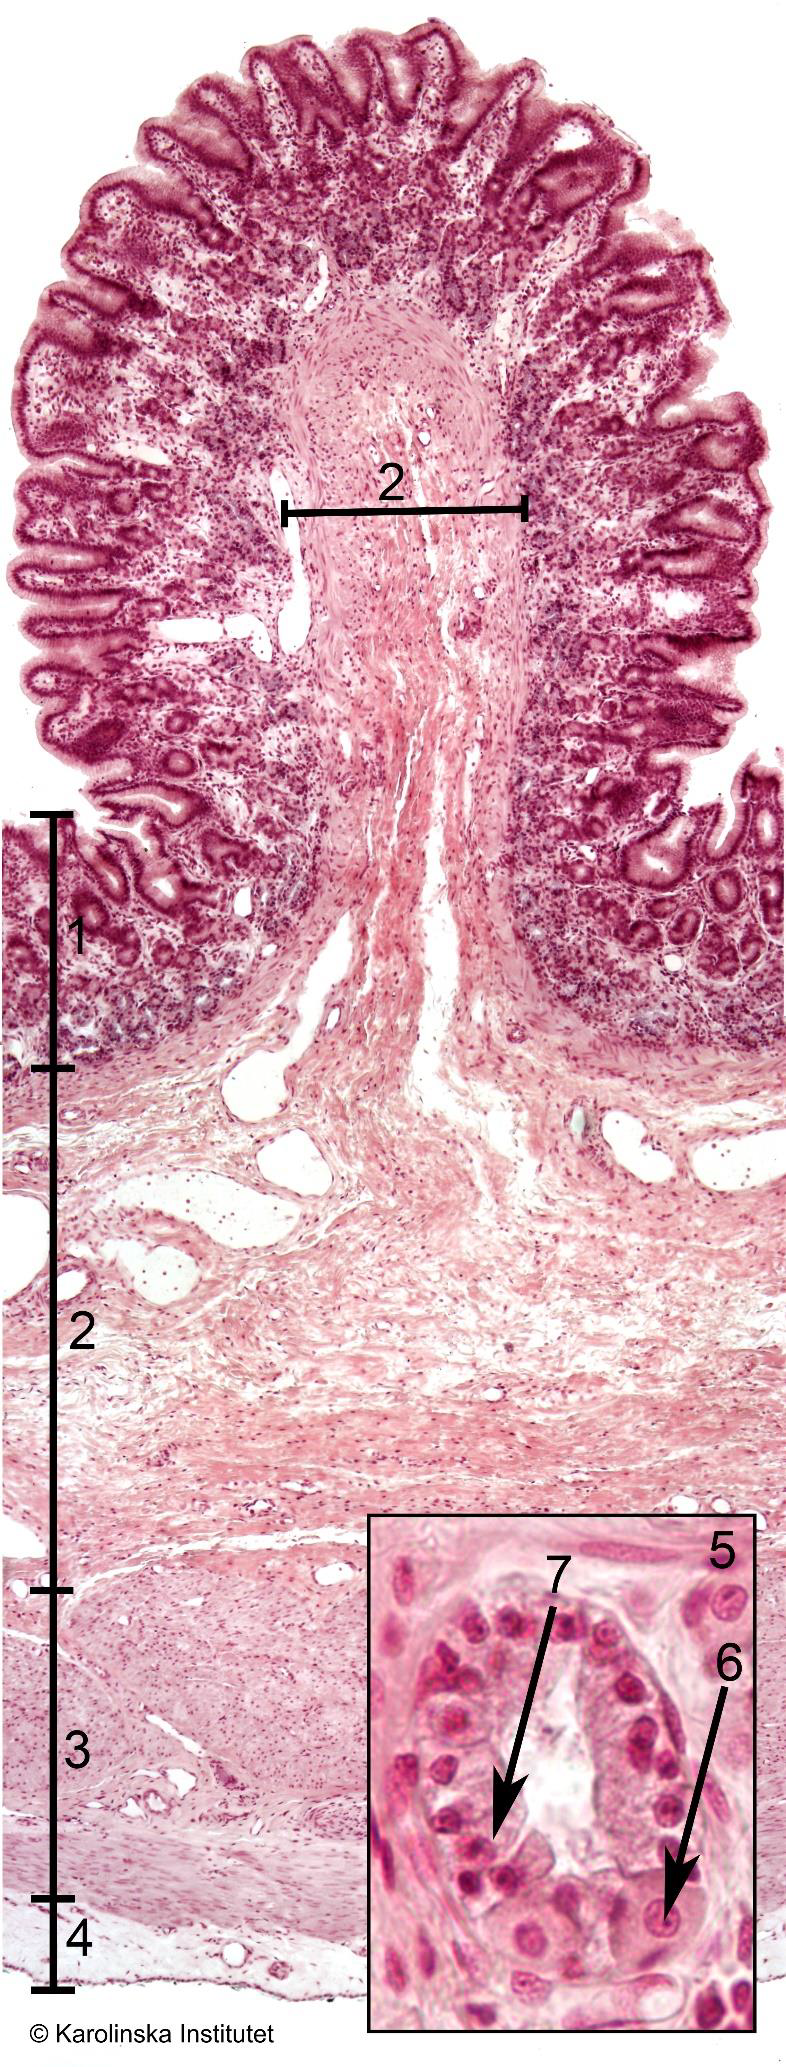

9. CapsulaStomach

1

2

3

4

51. Mucosa,

2. Submucosa,

3. Muscularis,

4. Fibrosa,

6. Parietal cell,Stomach